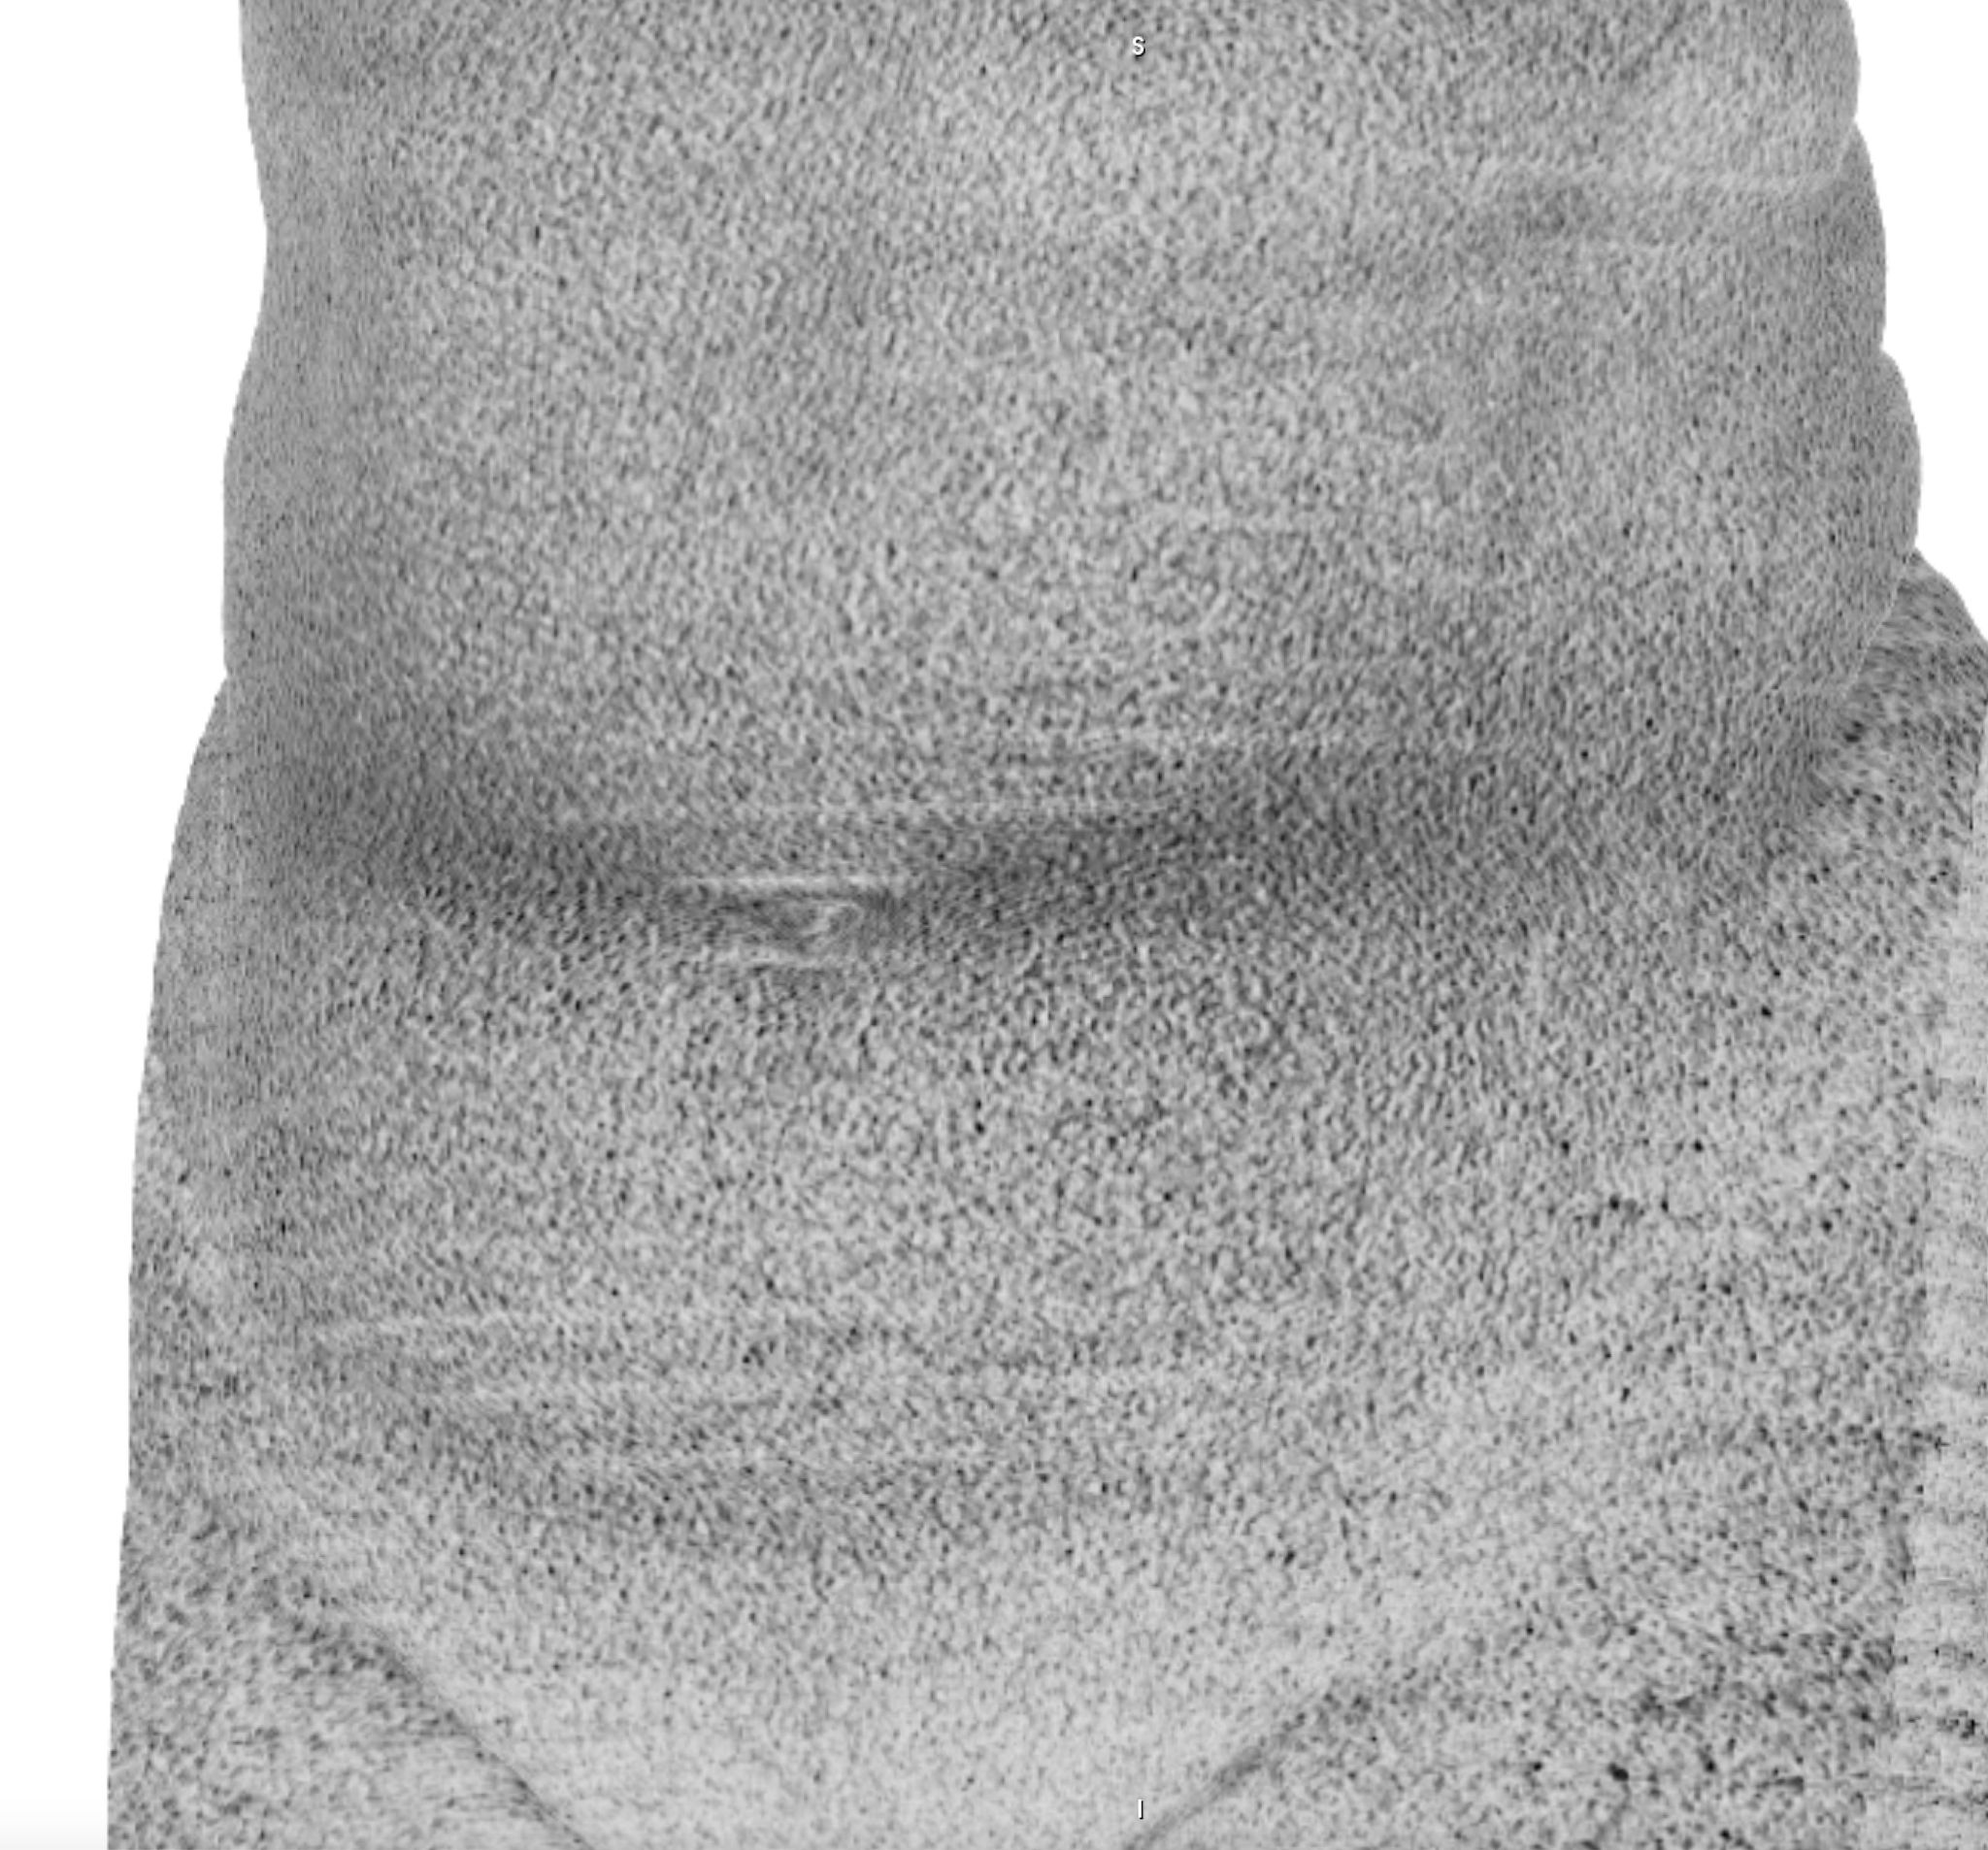

Chasing Intensities considers the body through its relationship to contemporary medical imaging technologies.

The history of medicine can be understood as an on-going endeavour to comprehensively visibilise the body, to pull it from obscurity, to open it out to vision. ‘The x-ray image, with its simultaneous view of the inside and outside, turned the vantage point of the spectator-subject inside out.’ * With the invention of the x-ray, the surface of the body, and its distinction from the world, was dissolved and lost in the image.

In this project, I look at the visual limit between the inside and the outside, the inner and the outer. I combine different visual approaches to materialise the body, using medical imagery, photography from manuals and radiology software. Decontextualised from their origin, these images speak of medicine’s relationship to both sex and violence, and remind us that, in medicine, to go into the body is always to go into the image first.